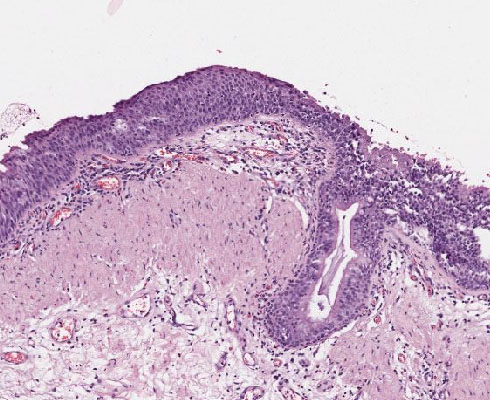

A14 Plattenepithelmetaplasie

Unreife plattenepitheliale Metaplasie der Bronchialschleimhaut, daneben respiratorisches Epithel mit Reservezellhyperplasie.